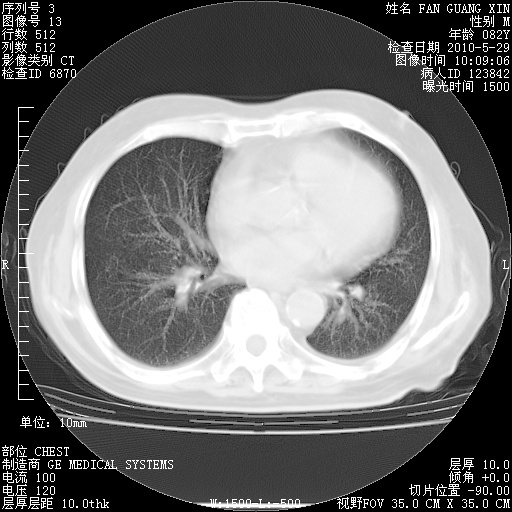

治疗3周后的肺部CT纵隔窗

从胸部影像学来看,的确有好转。至于目前为何发热不甚清楚?除了发热还有其他症状如有无喀痰,痰呈丝状吗?等等。尽量搜寻有无致发热其它可能原因?真菌?其它?如果的确无其他致发热的原因,考虑将甲强龙调至60-80mg bid/日。免疫全套基本无异常,考虑多系特发性肺间质纤维化